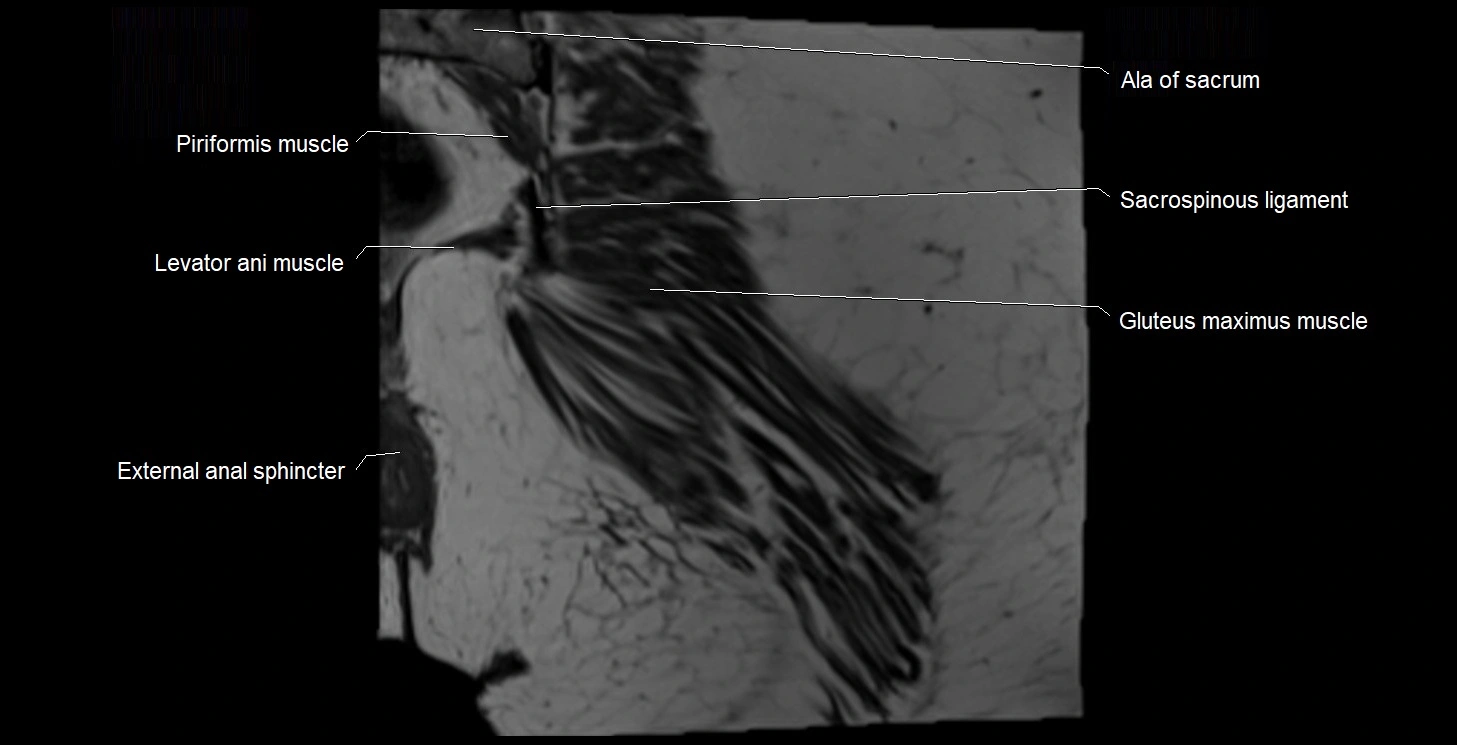

- Ala of sacrum

- External anal sphincter

- Gluteus maximus muscle

- Iliococcygeus muscle

- Levator ani muscle

- Sacrospinous ligament